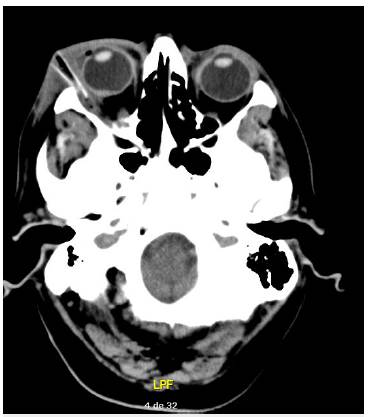

Hombre de 70 años que consulta al servicio de urgencias por cuadro clínico de 8 días, consistente en caída accidental de aproximadamente 2 m de altura en área rural, con trauma en región orbitaria derecha acompañado de dolor, edema palpebral, eritema, epifora, secreción purulenta y disminución de la agudeza visual. A la valoración encontramos celulitis orbitaria y periocular temporal derecha, defecto pupilar aferente ipsilateral y contracción mandibular derecha que limita la apertura oral. Se inicia tratamiento con antibióticos de amplio espectro y se realiza tomografía de cráneo simple y resonancia magnética de órbitas (figura 1) que muestra cuerpo extraño en la órbita derecha con extensión intra y extraconal, asociado con colección periocular derecha. Al tercer día de la hospitalización, oftalmología realiza extracción de cuerpo extraño y drenaje de colección, y se requiere monitorización en la unidad de cuidado intensivo.

Figura 1 Tac de cráneo simple corte axial, hallazgo de cuerpo extraño de la órbita derecha con cambios inflamatorios intra y extraconales.